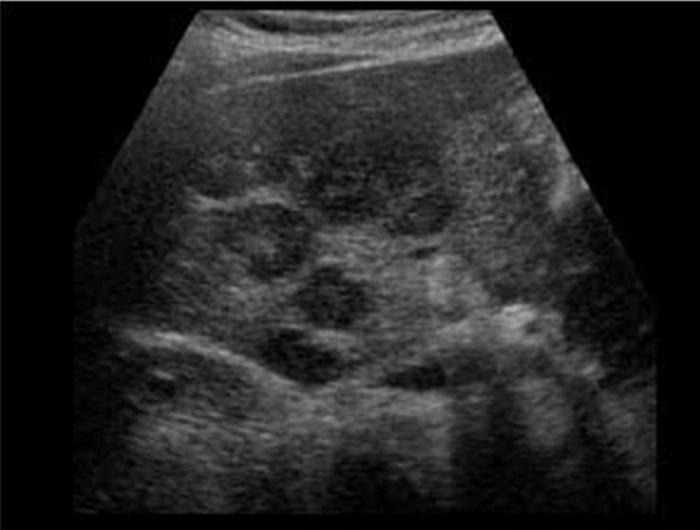

Liver mets from ?

Metastasis to the liver

colon

Most common

Liver mets from ?

Metastasis to the liver

Breast

Liver mets from ?

Metastasis to the liver

Lung

Liver mets from ?

Lymphoma